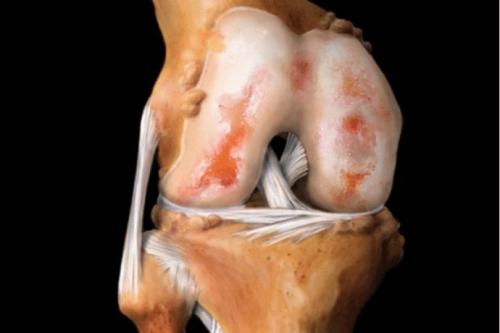

Вид на поражённую хрящевую поверхность.

Хрящ в коленной области – одна из самых сложных структур в организме человека, выполняющих ежедневное функциональное назначение, без которого невозможно представить себе нормальную жизнедеятельность и двигательную активность. Тонкий хрящ, покрывающий и предохраняющий поверхности костей, образующих коленный сустав, эластичен и призван сглаживать движения человека, исключая возможность межкостевого трения. Как и все остальные тонкие хрящи в суставах, он амортизирует испытываемые нагрузки.

Суставный хрящ

Суставный хрящ – сложное соединение, в состав которого входят вода, глюкозами, коллагеновые и эластиновые волокна. Отсутствие воды и недостаточная выработка глюкозама, полисахарида, представляющего собой неотъемлемую составляющую хрящевой ткани, приводит к утрате волокнами своих специфических свойств.